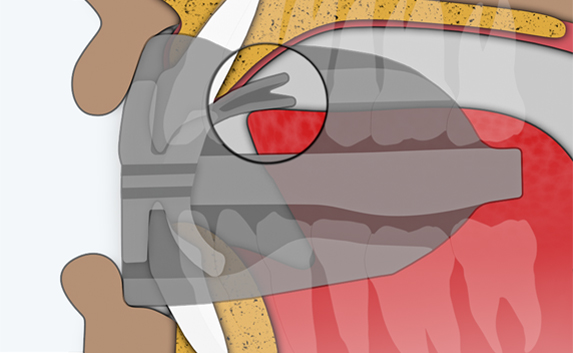

The Myosa®for TMJBDS®S1 is used in patients with a Breath Hold Time (BHT) of 20 seconds or more. It works by advancing the sleeper’s lower jaw and opening the bite, which has the effect of opening the airway. Additionally, the S1 has four breathing holes at the front to regulate breathing. For better retention during sleep, the patient can use the mouldable version of the S1 appliance (S1M). Progress to the S2 when the patient’s BHT reaches 35 seconds or more.